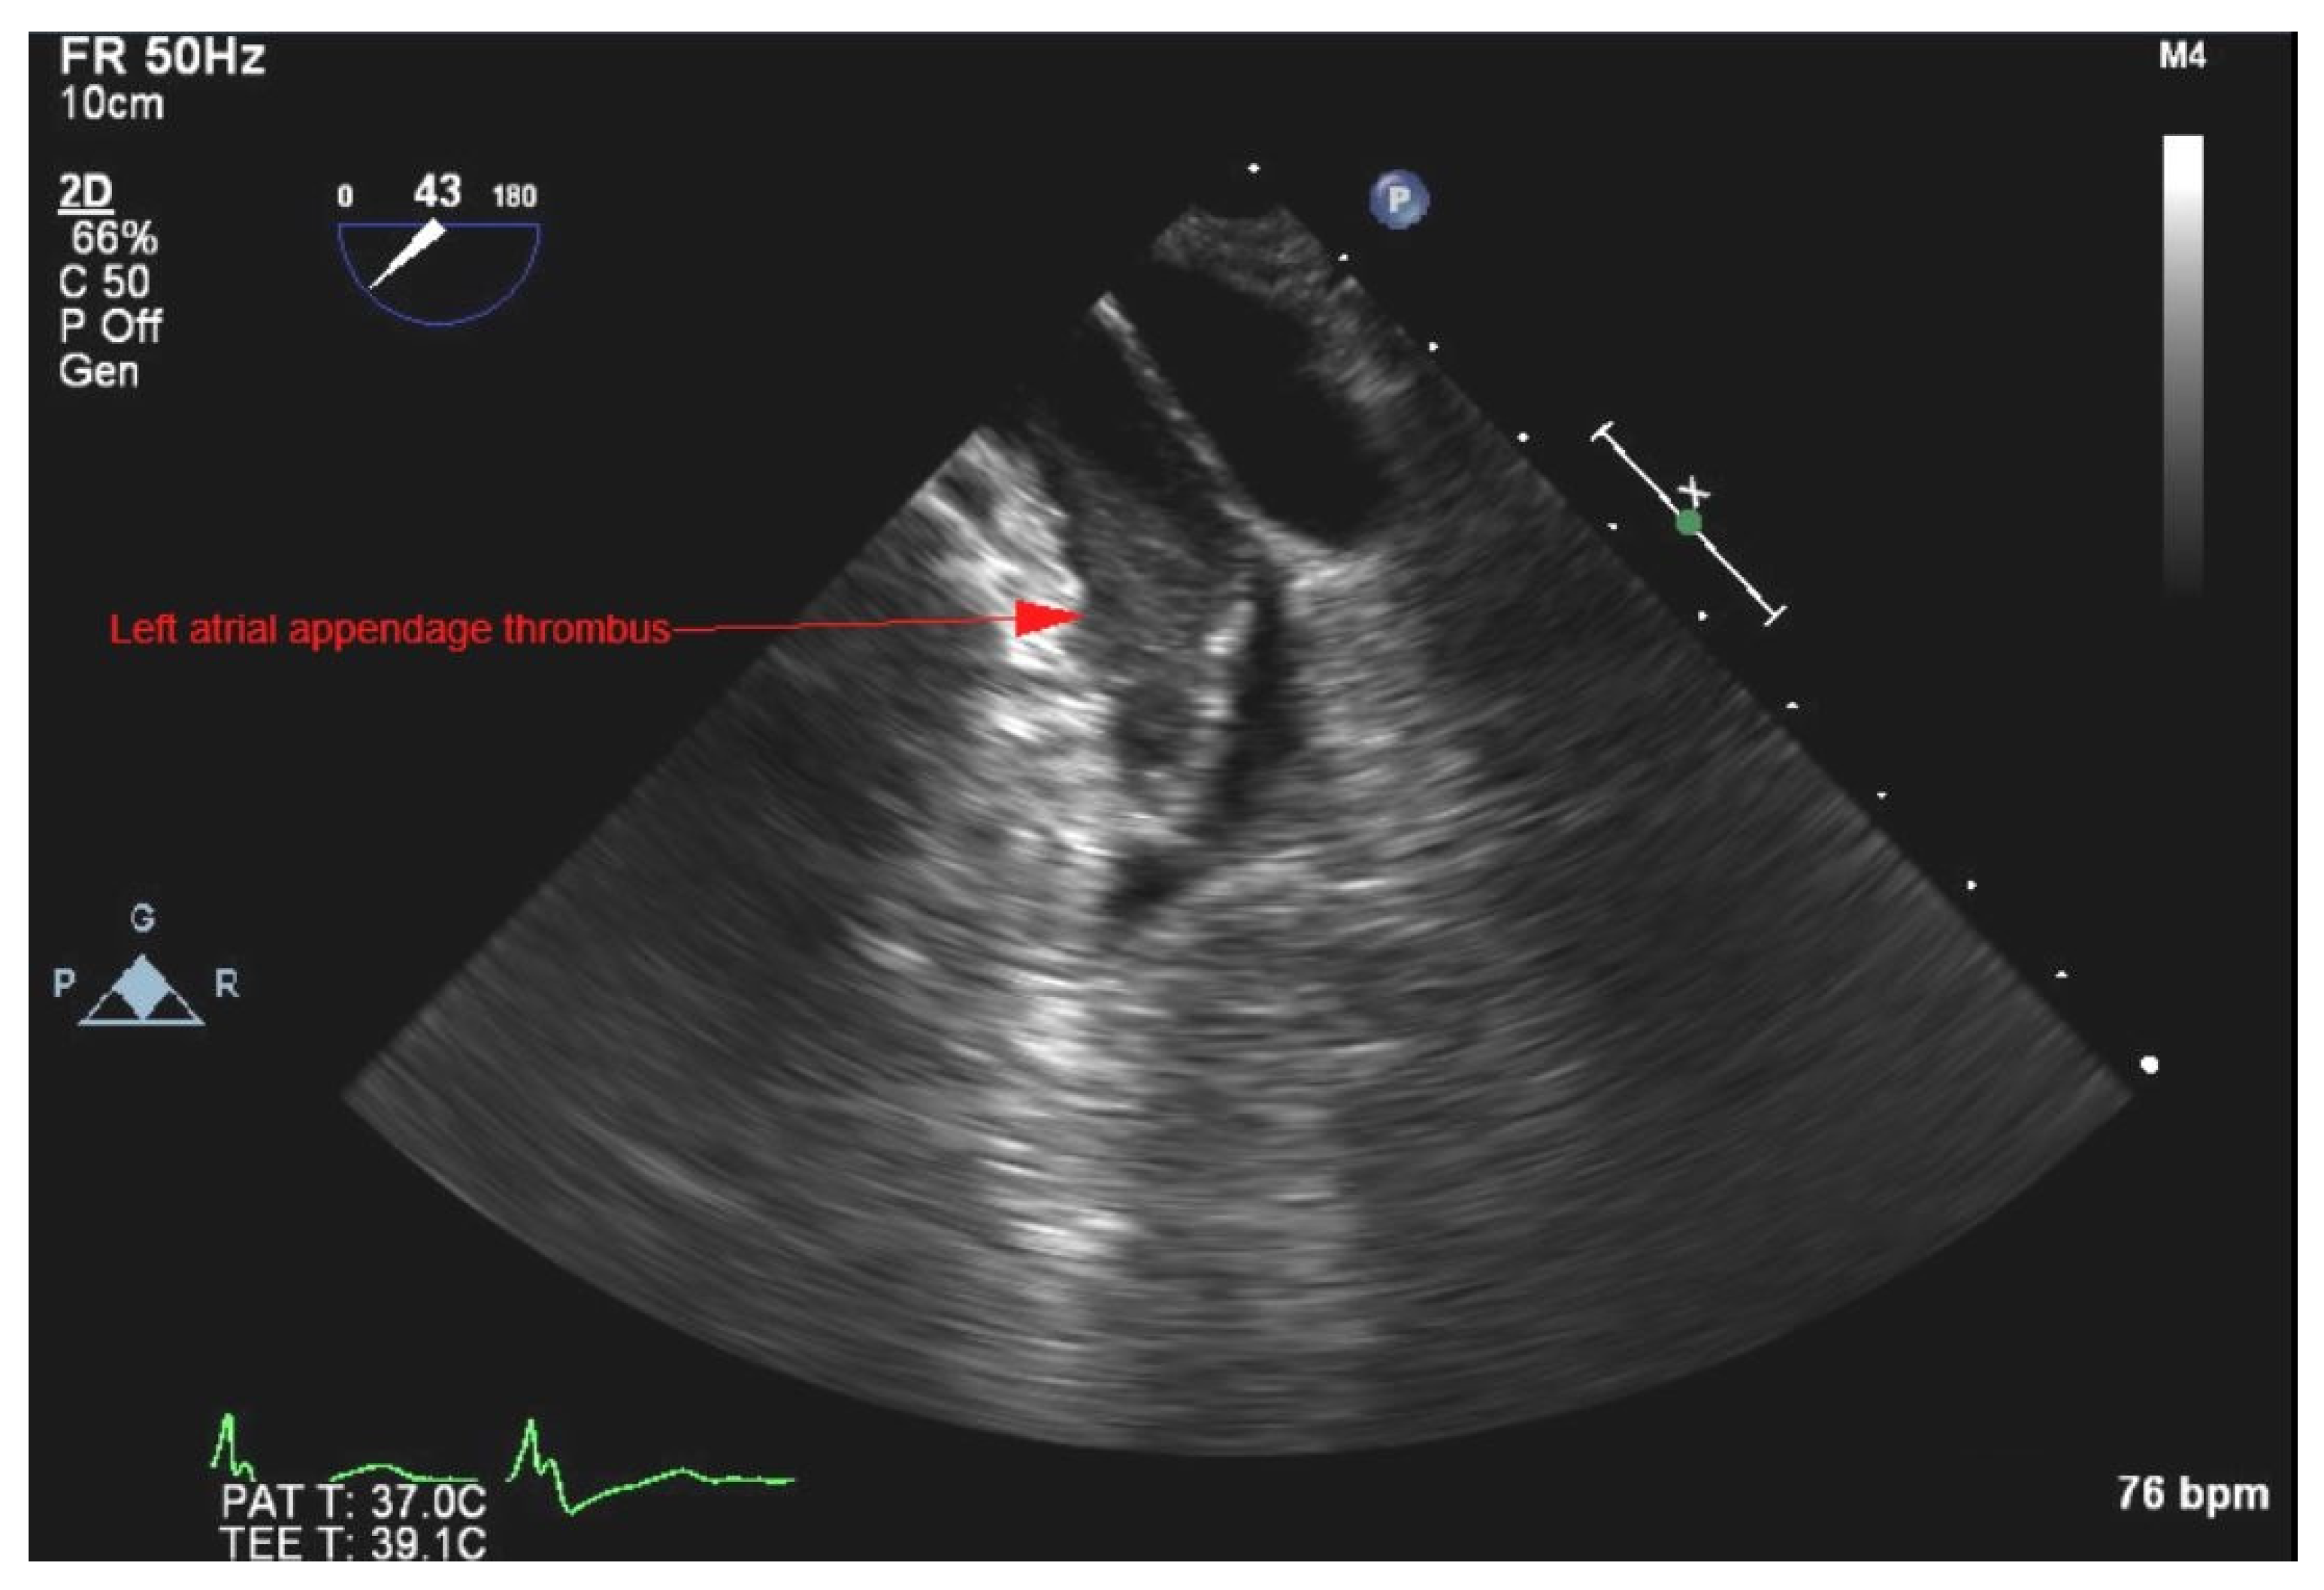

2. Case Presentation